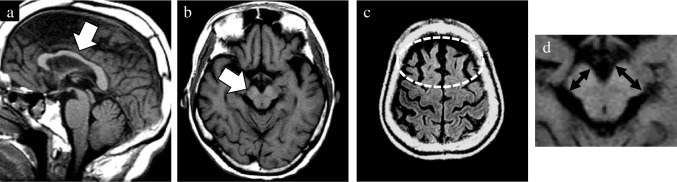

In addition to the well-established GCA and MTA scales, newly devised rating scales were utilized to evaluate the presence of midbrain atrophy and asymmetric atrophy. The degree of midbrain atrophy was assessed using a three-point scale (0 = normal, 1 = mild, and 2 = severe) primarily on sagittal T1WIs (Fig. 1). Mild midbrain atrophy indicated a slight reduction in the anteroposterior and/or superoinferior diameters. By contrast, a definitive decrease in these diameters was classified as severe midbrain atrophy. The degree of asymmetry in the frontal, temporal, parietal, and occipital lobes, along with the cerebral peduncle, was assessed using a three-point scale (0 = normal, 1 = mild, and 2 = severe) on axial T1WIs (Fig. 2). Severe asymmetry indicated the definite dilation of the sulcus and/or narrowing of the gyrus between the two hemispheres. Conversely, a case with unremarkable asymmetry was rated as mild.